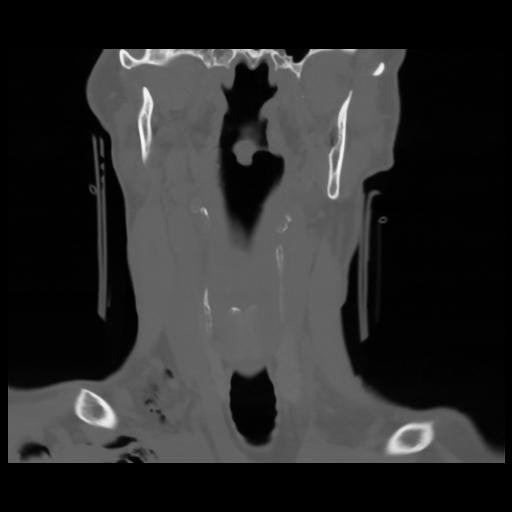

13 P.BLANDAS,,Coronal,2.000,P.BLANDAS,Coronal,